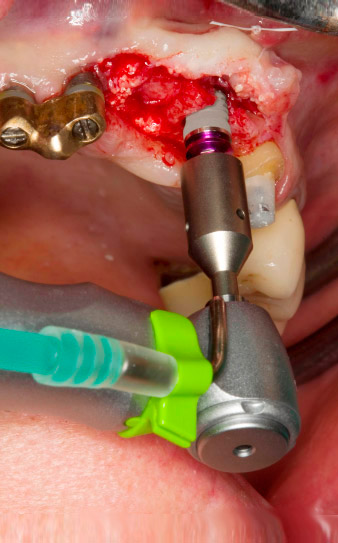

El hueso alveolar de la posición 22 resultó tener unas dimensiones suficientes. Las figuras 2 y 4 muestran la preparación del lecho del implante, el corte de rosca y la colocación del implante con el equipo Implantmed.

orificio piloto utilizando el nuevo Implantmed y el contra-ángulo WS-56 L

Imagen 2: Dos meses después, se practicó un orificio piloto utilizando el nuevo Implantmed y el contra-ángulo WS-56 L (programa P1, transmisión 1:1). La refrigeración se realizó a través del tubo de spray colocado a la izquierda (para diestros).